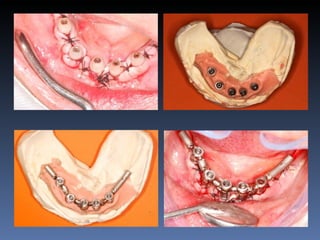

Maria Seemagenn Borges

Diagnóstico: Desdentada

Plano de tratamento: Instalação de 5 implants endo-

ósseos - “Protocolo Branemark”, com carga imediata.

Plano de tratamento: Exondontia de todos os dentes

mandibulares existentes, instalação de 5 implantes

endo-ósseos – Protocolo Branemark, com carga

imediata.